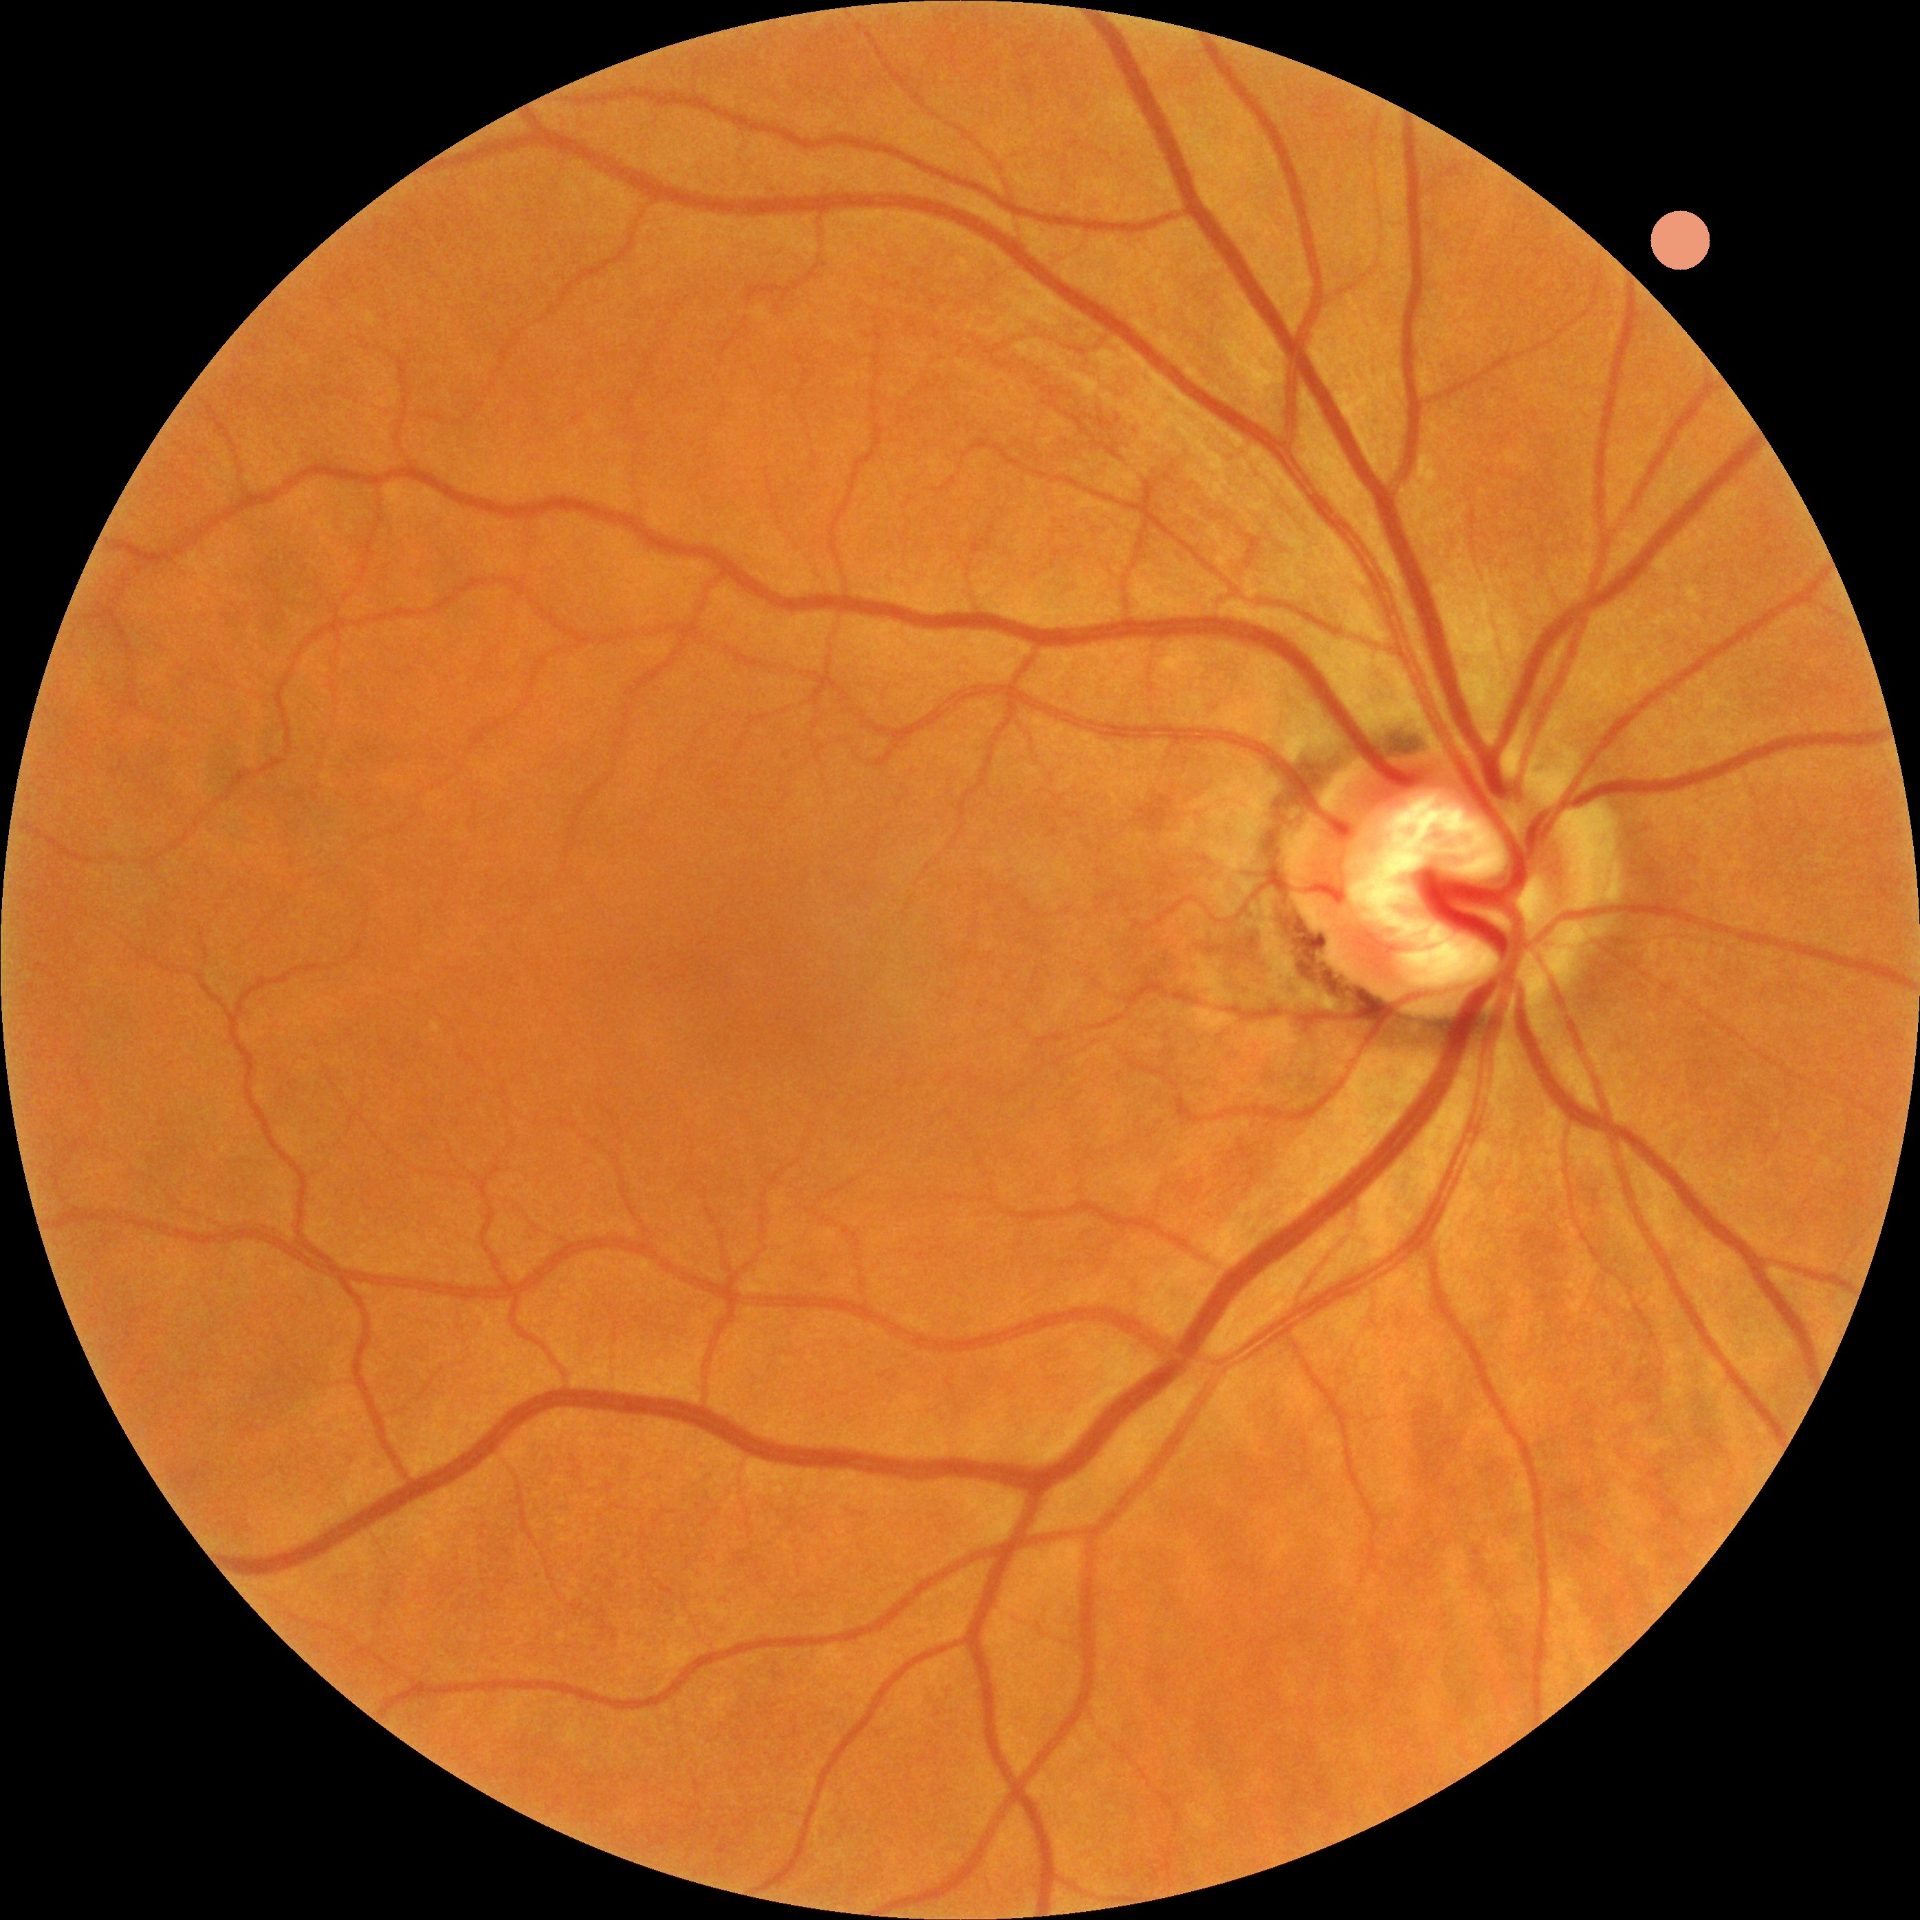

Inwendig oogonderzoek en netvliesscan

Tijdens het onderzoek controleren we de ogen grondig op afwijkingen. Met een biomicroscoop (spleetlamp) onderzoeken we de oogbol, traansamenstelling en oogleden. Bij het inwendige oogonderzoek gebruiken we pupilverwijdende druppels om een beter zicht te krijgen op het netvlies.

Verder maken we bijna altijd scans en foto's van uw netvlies. In sommige gevallen zijn aanvullende metingen nodig, zoals een gezichtsveldonderzoek. Hiervoor maken we dan een vervolgafspraak.